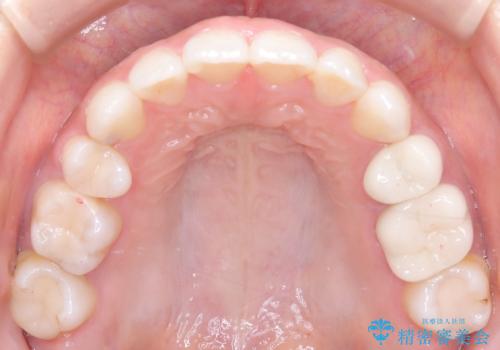

- 上下の歯の中心(正中)のズレと、口元の見た目を気にされて来院されました。精密な検査の結果、咬み合わせのバランスを整えながら、正中線を一致させる治療が必要と判断。患者様のご希望に合わせ、透明で目立ちにくいインビザライン(マウスピース矯正)による治療計画を立案しました。歯列全体を奥(遠心)へ移動させるためにゴムかけを併用。さらに、見た目を改善するため、既存の金属の被せ物をセラミッククラウンに交換することも治療計画に組み込みました。

今回の矯正治療では、透明なマウスピース型の装置インビザラインを使用しました。歯列を奥へ動かす遠心移動の効率を高めるため、患者様ご自身にゴムかけも行っていただきました。この併用によって、歯をより正確かつスムーズに動かすことができ、上下の歯の中心である正中線を一致させることが可能になりました。また、治療の最終段階では、以前から入っていた金属の被せ物を、天然歯に近い色合いのセラミッククラウンに交換。矯正治療と審美治療を組み合わせることで、機能的な咬み合わせの改善に加え、金属が見えない、より自然で美しい口元を獲得していただけました。